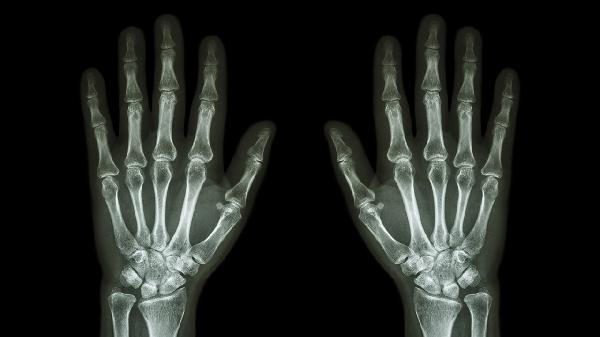

手指關(guān)節(jié)處突然烏青可能是由外傷、血液疾病或血管異常等原因引起的。烏青通常表現(xiàn)為皮下出血,可能伴有疼痛或腫脹,建議及時就醫(yī)明確原因。

手指關(guān)節(jié)處受到撞擊、擠壓或扭傷可能導(dǎo)致毛細血管破裂,形成烏青。輕微外傷引起的烏青通常會在1-2周內(nèi)自行消退,期間可冷敷減輕腫脹。若疼痛持續(xù)加重或伴有活動受限,需排除骨折或韌帶損傷。